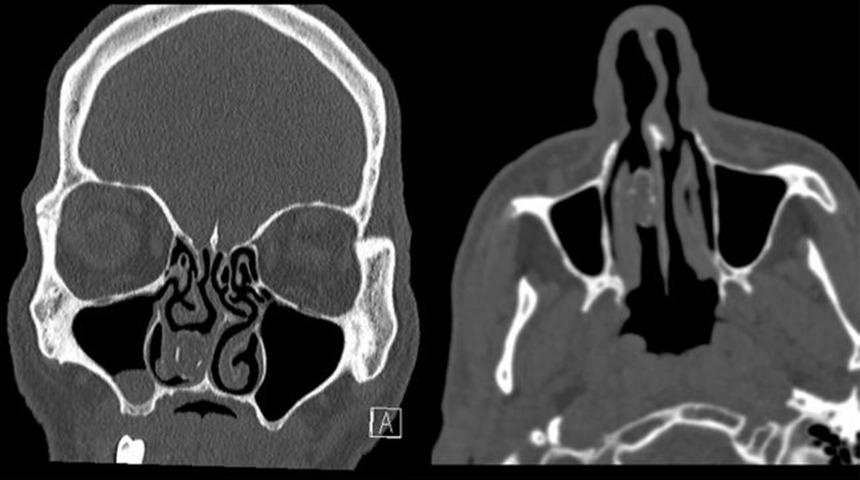

Live Science'da yer alan habere göre, Sydney kentinde Westmead hastanesine başvuran adam şikayetlerini doktora anlattıktan sonra tetkikler yapıldı. Yapılan taramalar sonucu adamın burnunda sıkı gri bir kütle görüldü.

Araştırmalar sonucunda burnundaki kütlenin bir paket içinde bulunan esrar olduğu ortaya çıktı.